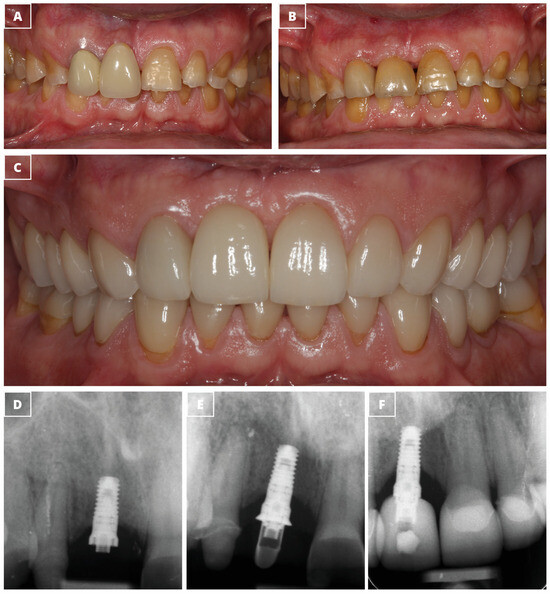

Retrospective Study of Functional and Esthetic Outcomes Using Narrow-Diameter Implants for Single Upper Central Incisor Replacements

3. Results